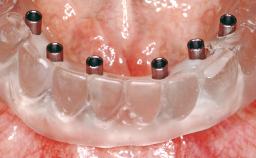

Immediate Loading of Six Implants in the Maxilla and Final Restoration with a Full-Arch CAD/CAM Zirconia FDP

A 63-year-old male patient was referred for a consultation and treatment of partial edentulism in the maxilla. The patient presented with residual anterior teeth and declined a partial removable prosthesis. He reported that the maxillary posterior teeth had been extracted due to mobility and periodontal disease two months before the consultation. The patient’s chief complaint was that his residual maxillary teeth were mobile and that he was unable to chew. The patient’s desire was a stable and comfortable fixed maxillary rehabilitation. The patient was a light smoker (fewer than 10 cigarettes/ day), and his medical history was without significant findings. He was not on any regular medication at the time of consultation. The extraoral examination revealed a normal physiognomy with a correct distribution of the facial thirds. The patient presented a low lip line, and the transition line between teeth and soft tissues was not exposed during a forced smile.

# of Implants 6

Type of Implants One-Piece

Modality 6+ implants with immediate loading

Loading Protocol Immediate